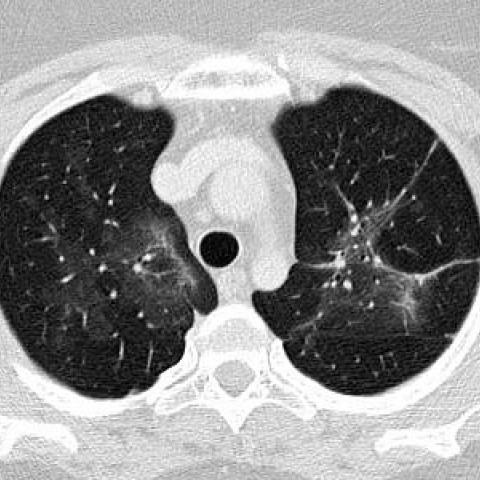

1、诊断:医生会根据患者的症状、体征、实验室检查和影像学检查等综合判断,确诊是否为肺炎。